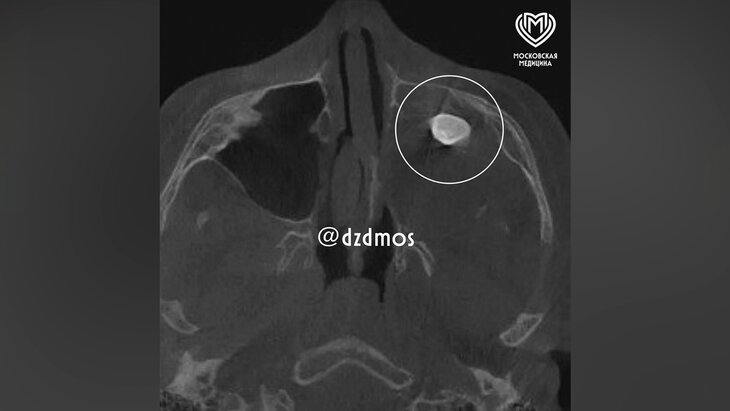

Фото: телеграм-канал "Московская медицина"

Врачи Филатовской больницы в Москве вытащили зуб из носа 15-летнего мальчика. Об этом сообщила пресс-служба департамента здравоохранения столицы.

Юный пациент поступил в медучреждение с жалобами на асимметрию лица и заложенность носа. По словам хирурга-оториноларинголога Вугара Достиева, ранее мальчику уже проводили осмотр в частной клинике, в ходе которого обнаружили в гайморовой пазухе сформированный зуб.

Исследование показало, что у подростка была тератома – эмбрионально-клеточное опухолевое образование, которое может содержать ткани различных органов. Как отметил Достиев, такие новообразования очень редко располагаются в зоне лица. В случае подростка тератома занимала практически всю левую полость носа, из-за чего ее не смогли показать ни КТ, ни рентген.